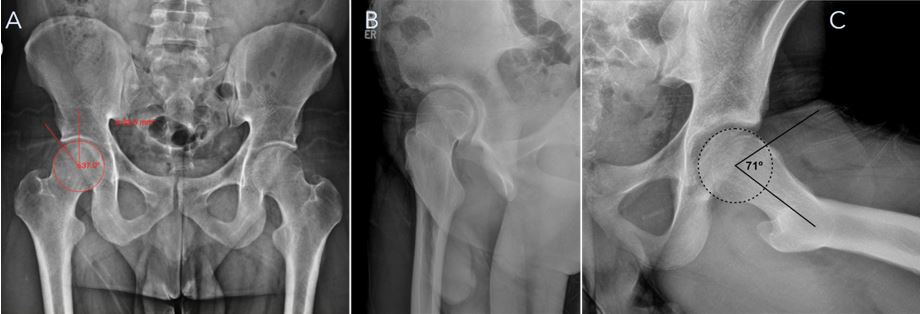

En cuanto a la radiografía, principalmente se utilizan tres proyecciones: anteroposterior de pelvis (Fig. 4A), para evaluar el desgaste articular y la cobertura del acetábulo respecto de la cabeza femoral. El ángulo lateral centro-borde (lateral center-edge angle, LCEA, sus siglas en inglés) o ángulo de Wiberg permite determinar si la cobertura es normal o patológica. En este contexto, una cobertura excesiva del acetábulo puede indicar la presencia de una deformidad tipo Pincer, mientras que una cobertura insuficiente podría sugerir displasia de cadera. La proyección denominada “falso perfil” (Fig. 4B) se utiliza para evaluar patologías en la parte anterior del acetábulo. Finalmente, la proyección de Dunn (Fig. 4C) es útil para observar deformidades tipo Cam, y se mide el ángulo alfa para determinar si existe una deformidad en la unión cuello-cabeza del fémur.

Figura 4. A) Proyección anteroposterior de pelvis con la medición del ángulo lateral centro-borde o de Wiberg, con valores normales entre 25 y 40°. B) Proyección de falso perfil, útil para evaluar lesiones en la parte anterior del acetábulo. C) Proyección de Dunn, en la que se observa el ángulo alfa para detectar lesiones tipo Cam en la unión cuello-cabeza del fémur. Se considera patológico un ángulo superior a 55°